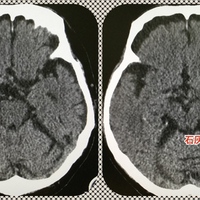

MMさんは84歳の男性である。 当院のもの忘れ外来を受診したが、長谷川式テストはほぼ満点だった。認知症の可能性はほぼなかったのだが、「記憶が飛ぶ」、「ボーッとしている」という訴えから、認知症ではない別の病気の可能性が浮上した。